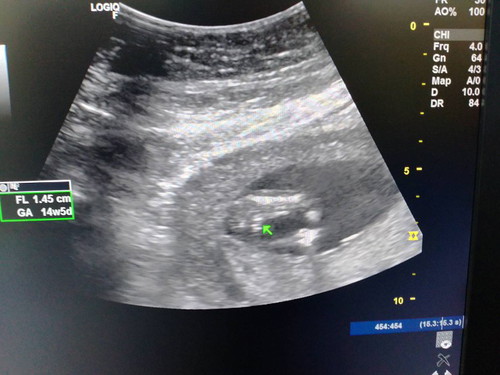

หมอบอกลูกสาวชัวร์ แม่ดีใจมาก อยากได้ลูกสาว ขอดูภาพอัลตราซาวของแม่ๆหน่อยค่ะ ได้เพศไหนกันบ้าง ?? 14w+5d